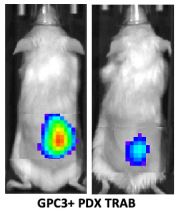

📡fresh off the press 📡 @MCT_AACR GPC3-targeting optical probe and T-cell redirecting antibody as a #theranostic strategy for detection and treatment of #HCC validated in patient-derived xenografts @PennRadiology @PigiLab @SIRspecialists @MDAndersonNews